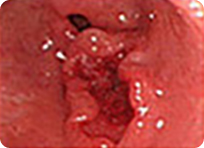

매우 작고 미세한 변화만을 보이는 조기위암들

풍부한 내시경 경험을 가진 의료진이 최신의 내시경 기계를 이용하여 세심한 관찰을 해야 위와 같은 매우 작은 조직 위암을 놓치지 않고 진단할 수 있습니다.

조기 위암의 경우 대부분 증상이 없으며 증상이 있어도 단순한 속 쓰림이나 소화불량증과 구별이 안됩니다.

조기 위암이 진행이 되어 진행성 위암이 되어야만 비로소 구토, 복통, 체중 감소, 소화불량, 토혈 등 여러 가지 증상이 나타나게 됩니다.

조기 위암과 같이 위암을 초기에 발견할 경우 완치가 가능하나 진행성 위암과 같이 암이 많이 진행되어 발견될 경우는 현대 의학으로도 치료할 수 없습니다.

전문가에 의한 위내시경 검사는 수 mm 크기의 조기 위암도 정확히 진단할 수 있습니다. 특히 색소를 이용한 색소 내시경의 경우 육안적으로 구별하기 힘든 병변도 정확히 진단할 수 있습니다.